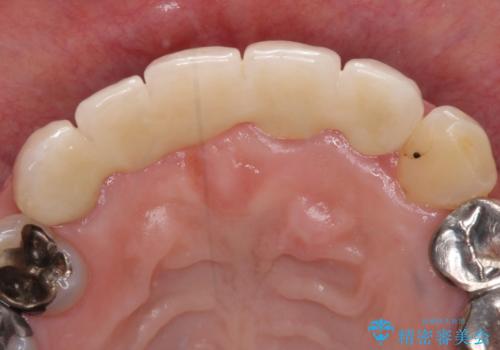

- 前歯のブリッジ治療中に装着していた仮歯が、あまりにも不自然で気になるとのことで来院された患者様です。

早急に仮歯をきれいなものに付け替え、オールセラミックブリッジにより補綴することとしました。

オールセラミッククラウンは、本物の歯のような外観となり、患者様には大変満足していただけました。